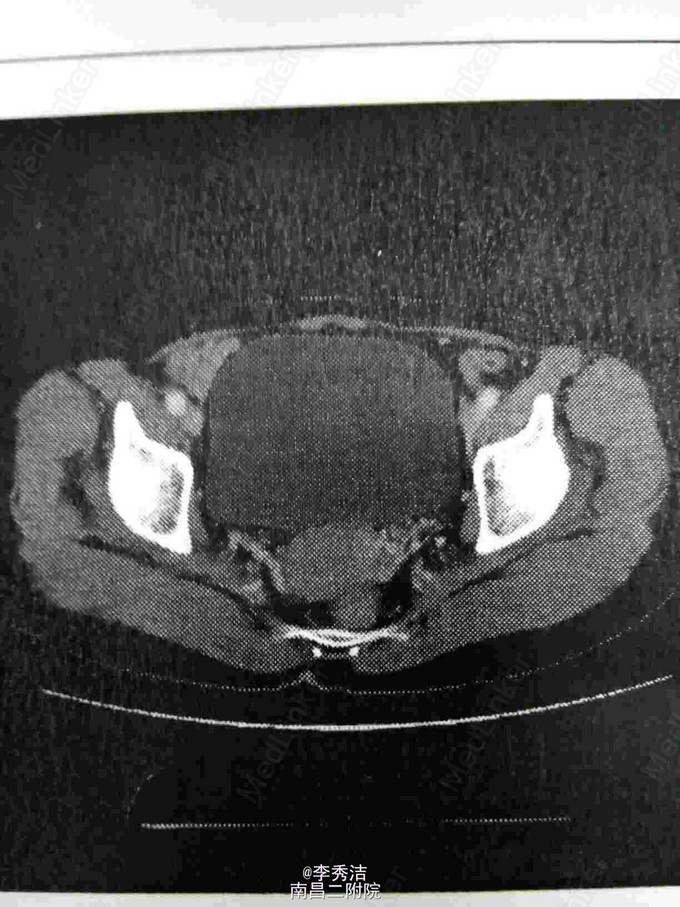

患者女,55岁,一周前体检发现宫颈癌,无任何自觉症状。诊断性刮宫病理结果示:子宫颈中分化浸润性磷状细胞癌。给予全子宫+双附件切除加盆腔淋巴结清扫,后期予顺铂+紫杉醇化疗。